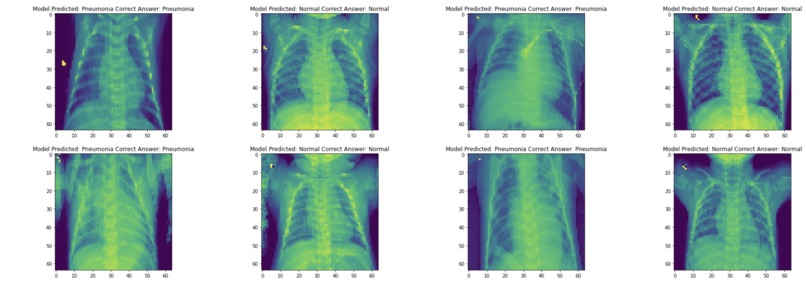

We designed an AI algorithm to actually take patient ultrasounds or any scan in general and use machine learning to train the module to detect some of the more common issues we see in hospitals. Specifically, use a piece of technology known as Convolutional Neural Networks.